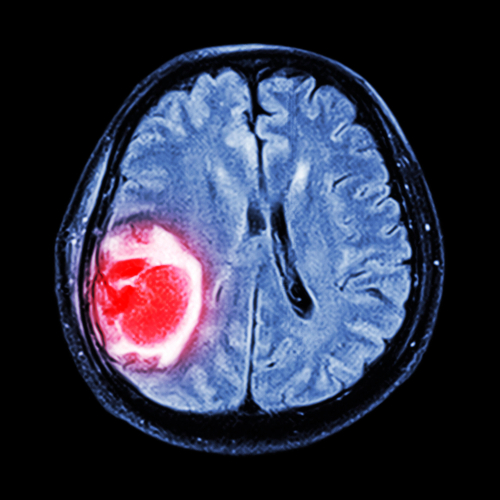

يحاول باحثون تعزيز فعالية الفيروسات القاتلة للسرطان؛ لعلاج حالات تشمل أورام المخ (يظهر بالأحمر).